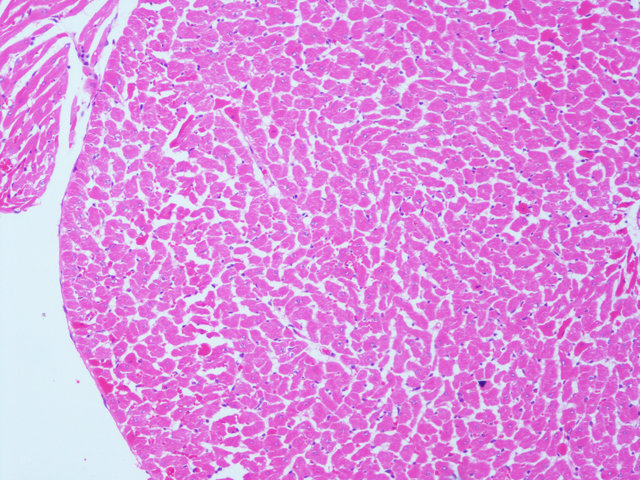

病理学的所有切片,都必须通过一种以上的染料,通过各种不同的方法,将切片中各种不同的物质,在不同染液的作用下,将其显示出来,使之在光学显微镜下,能够完全的观看各种结构。例如,HE染色,好质量的切片可以清晰地显示出许多不同的结构,细胞核着蓝黑色,细胞浆着粉红色,软骨着蓝色等。清晰的结构为诊断提供可靠的依据,因此,染色技术也是病理技术中的重要组成部分,必须不断地总结,方能提高。如果染色不好,切片染色一团糟,红蓝不分,结构不清,层次不明,影响了镜下的观察,直接影响了临床诊断,染色结果的好坏直接关系到诊断的准确性。

(25)中性树胶封固。结果:细胞核被染成深蓝黑色;细胞浆被染成粉红色;软骨及钙盐被染成蓝色;胶原纤维染成淡粉红色,嗜酸性细胞及嗜酸性颗粒呈鲜红色;弹力纤维呈淡粉红色;某些蛋白性物呈粉红色等。

样片参考:

肌肉横截面

心脏

HE染色 | 染色含切片 | 苏木.精-伊红染色法,观察组织形态 |